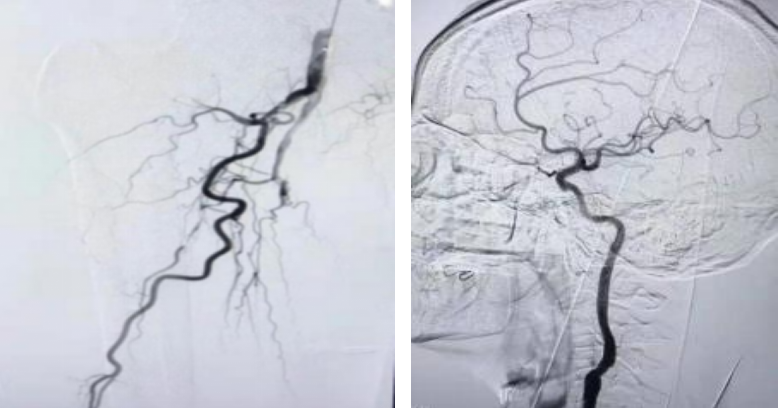

3. 多样化的外周血管疾病治疗:目前面临多种类型的外周血管病变,如:颈动脉体瘤、颈内动脉狭窄、下肢动脉硬化闭塞症、肺栓塞、下肢深静脉血栓、肠系膜上动脉夹层等疾病,我科能根据患者病情制定个体化治疗方案,采取介入手术与开放手术相结合的治疗模式,为患者选择最优治疗方案,提高疾病治愈率,降低并发症发生率,明显改善患者预后